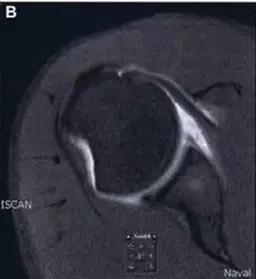

8. Segond 骨折和反向 Segond 骨折

(1)Segond 骨折

是发生在胫骨平台外侧的垂直撕脱性骨折。这种骨折在前后位 X 线片上显示最佳。屈曲位时膝关节受到内旋*力暴**作用,导致皮质骨撕脱性骨折,这种骨折常发生在运动员身上。

常引起股骨内髁和胫骨平台后内侧骨挫伤,75%~100% 的患者伴前交叉韧带断裂,33% 的患者伴外侧半月板损伤。

一位足球运动员的 Segond 骨折。A 正位片示关节线下方胫骨外侧皮质撕脱(箭头)。B MRI 冠状位 T1 加权像示附着于髂胫带的骨折碎片(空箭头)(来源:Radiol Clin N Am 53 (2015) 737–755,YU,Ohio)